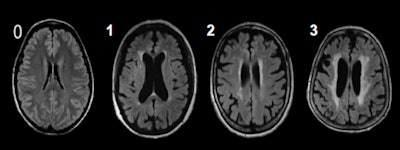

The Fazekas scale is a system for describing white-matter disease severity. It can quantify the amount of white-matter T2 hyperintense lesions attributed to chronic small vessel ischemia. Image courtesy of Dr. Tina Stegmann.A subgroup of 2,490 people additionally underwent brain MRI. Most of them had no or mild white-matter lesions (87%), and 13% had moderate or severe white-matter lesions.

The investigators sought to determine the frequency and associated risk factors for white-matter lesions in a population cohort and potentially discover a connection with heart failure. They used the Fazekas score for the classification of the white-matter lesions, and raters were blinded to other medical information of study participants. History of heart failure and other diseases were ascertained as part of the self-reported medical history questionnaire.